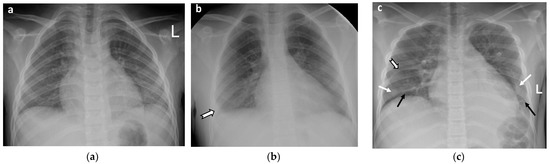

- Cardiovascular abnormalities including cardiomegaly (Figure 1c) and signs of pericarditis, myocarditis, and pericardial effusion.